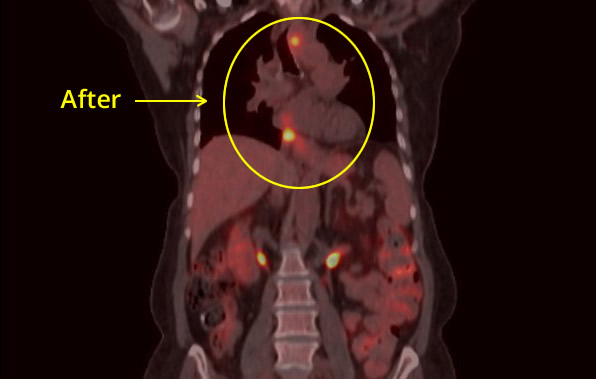

Esophageal CXR Before

Esophageal CXR After